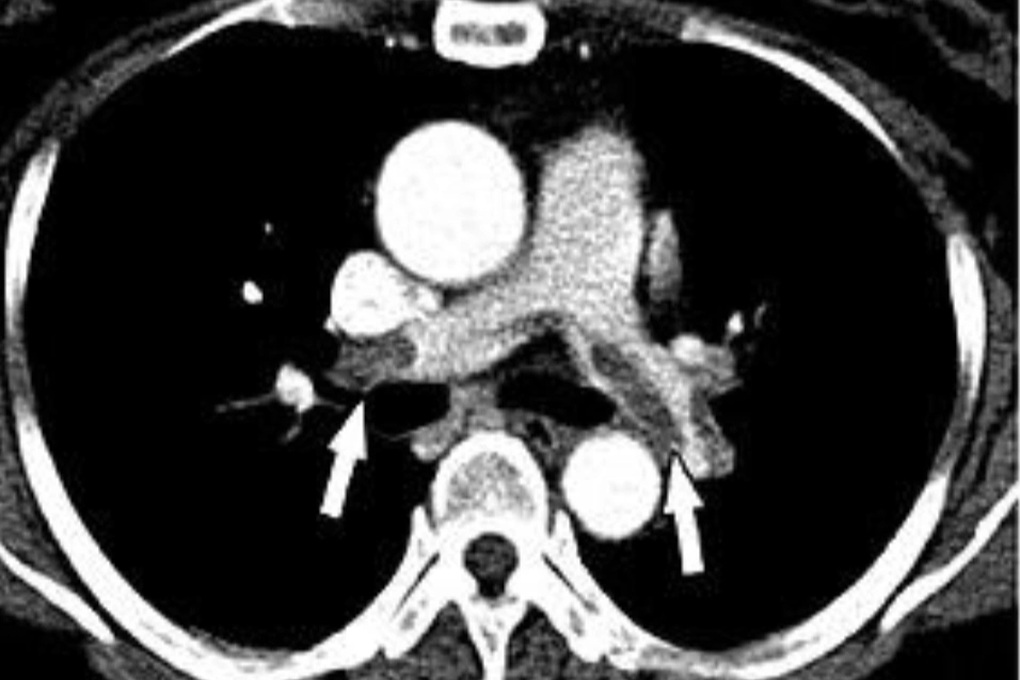

Kết quả siêu âm tim cho thấy bệnh nhân giãn thất phải có đè ép thất trái, ảnh CT ngực ghi nhận tình trạng thuyên tắc nhiều nhánh động mạch phổi 2 bên.

Kết quả CT cho thấy bệnh nhân thuyên tắc động mạch phổi 2 bên (Ảnh: BS).